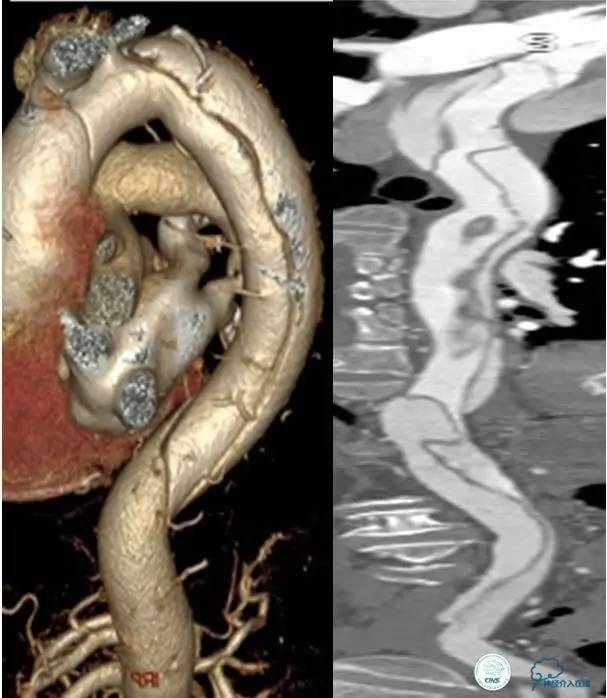

▼主动脉全程CT

中间诊断:

主动脉夹层 De Bakey Ⅰ型

脑梗死

治疗原则:

继续监测血流动力学指标

绝对卧床、控制血压、强效镇静与镇痛

急请血管外科会诊